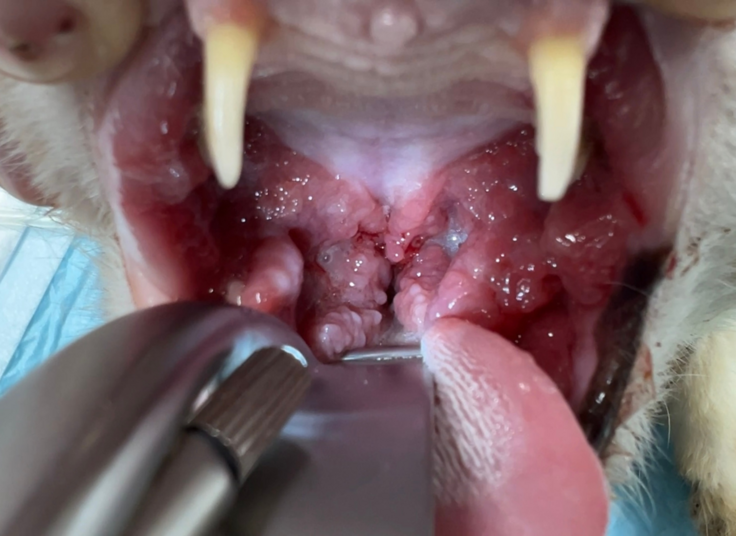

最近では、口臭と出血があり、ごはんも満足に食べられない状態の猫さんが保護されました。診察の結果、重度の歯周病で、歯科レントゲンでは歯根がすでに溶けていることが確認されたため、全臼歯抜歯の処置を行いました。

【処置後の写真:臼歯抜歯後、縫合処置をしました】

ご支援で導入した設備を使って、安全かつ短時間で全臼歯の抜歯を実施。術後はやわらかいごはんをしっかり食べられるようになり、今では穏やかな表情で日向ぼっこを楽しんでいます。

この他にも歯周病の猫さんの一部には、尾側口内炎と呼ばれる難治性の口内炎を患ってしまうことがあります。この場合、全臼歯抜歯に加えてレーザーによる炎症のコントロールも必要になります。口の中で食べ物がぶつかって痛いという苦痛に加えて、のど(咽頭部)にも痛みが出るため、食べることを拒絶したり、その痛みのせいで性格がきつくなってしまう子もいます。

【重度尾側口内炎によりのどに強い炎症がある猫さん】